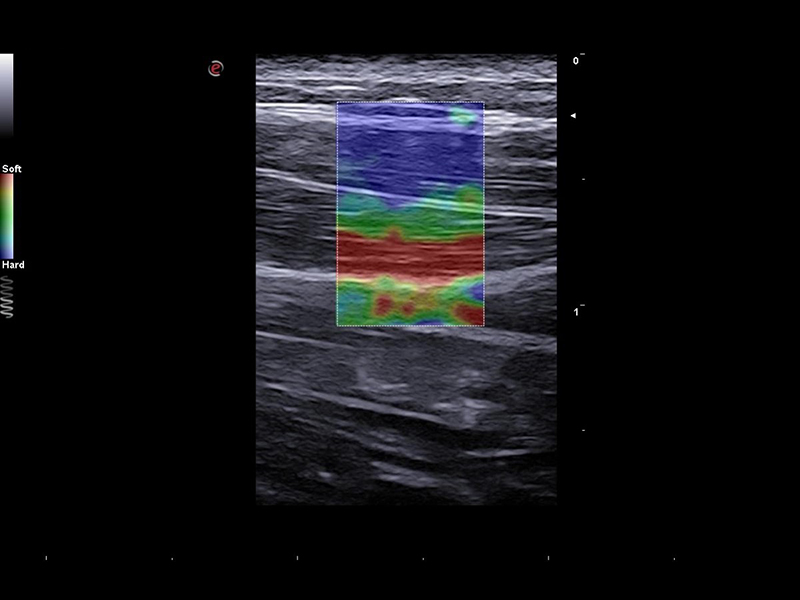

Elastosonography is particularly important in musculoskeletal applications because it provides valuable information about the mechanical properties of soft tissues in the musculoskeletal system. The ability to assess tissue elasticity is crucial in the diagnosis, monitoring, and management of various musculoskeletal conditions. ElaXto is the Esaote real-time, non-invasive strain elastography tool that allows you to assess tissue stiffness at a glance, thanks to a colour-coded stiffness mapping. Instead, QElaXto 2D, shear-wave elastography, is an Esaote technology that provides an immediate quantitative value of tissue elasticity, which can be particularly interesting in the follow-up of tendon injuries.